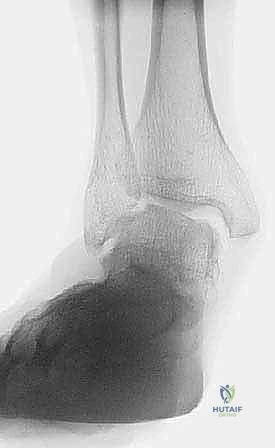

Clinical & Radiographic Imaging